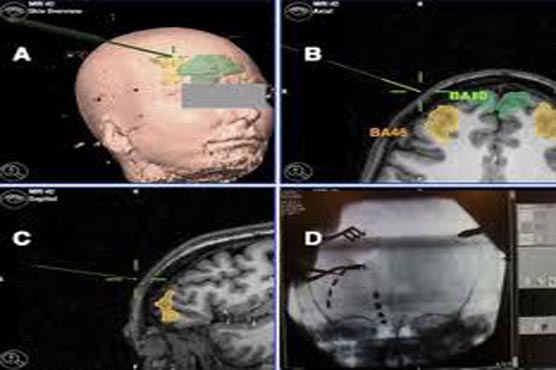

The trial involved implanting electrodes into the part of the brain that regulates emotion so as to moderate the activity of dysfunctional brain circuits. The device, which works similar to a pacemaker, was connected to a pulse generator implanted under the skin.